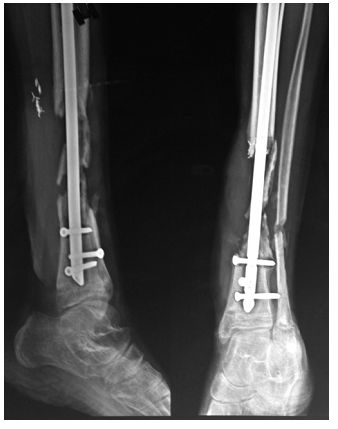

胫骨骨不连临床并不少见,下图为以19岁男性,髓内钉固定后发生感染性骨不连。